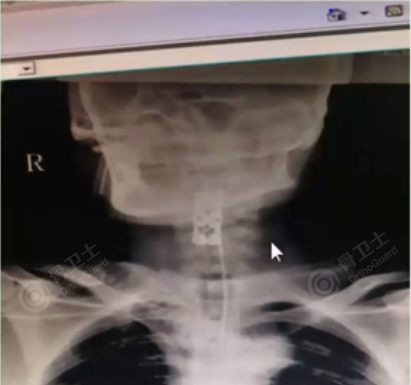

患者女,被高空坠物砸伤,致高位颈椎骨折、脊髓损伤伴高位截瘫、头皮挫裂伤、失血性休克、脑震荡。

640 (16).png

640 (17).png

▲患者术前影像

患者入院后,立即上呼吸机,进行抗感染和挽救脊髓的药物治疗,于当晚实施颈椎前路减压内固定术。术后使用甲强龙、神经节苷脂、神经生长因子、维生素B族、纳络酮以及改善循环的中成药、针灸和高压氧等综合治疗,同时采用促红素治疗。近三年研究发现,促红素可改善脊髓损伤的预后,并能促进中央干细胞转为神经干细胞。

患者术后恢复较为理想,基本感觉恢复到70%-80%,脚能抬起来,但上肢运动力量仍为零级。